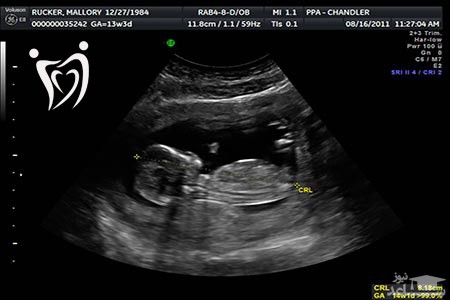

تشخیص شکاف کام در سونوگرافی

مادران باردار از طریق سونوگرافی سه بعدی می توانند به تشخیص شکاف کام کمک کنند. لذا توصیه می شود خانواده هایی که شکاف کام و لب را به صورت وراثتی دارند نسبت به انجام سونوگرافی در دوران بارداری اهتمام بیشتری داشته باشند.

از طریق آزمایش خون مادر نمی توان به شکاف کام و لب جنین پی برد. بنابراین بهترین راه شناسایی شکاف کام ، تشخیص شکاف کام در سونوگرافی می باشد.